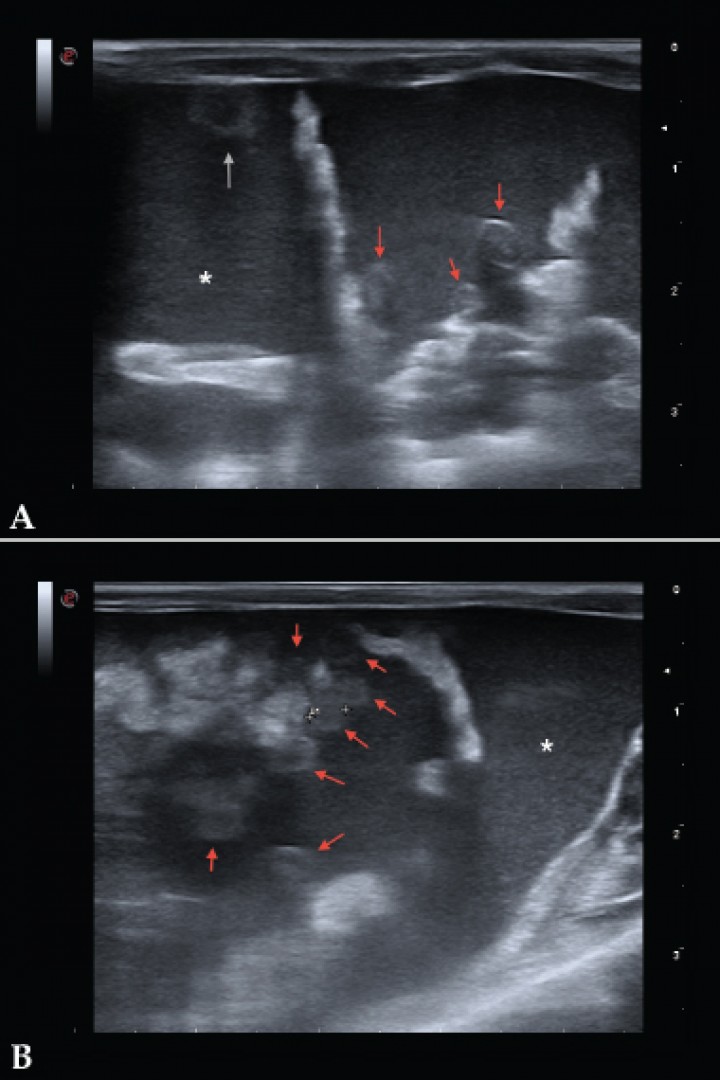

El examen físico confirmó la distensión abdominal con ausencia de masas palpables (Fig. 1). La radiografía mostró una pérdida de visualización de serosas y leve meteorismo, compatible con ascitis. Se procedió a la sedación de la paciente con 2 mg/kg de midazolam s.c. (Midazolam Normon, Tres Cantos) para el estudio ecográfico. La ecografía reveló gran cantidad de líquido libre abdominal con ecos internos, sugerente de alta celularidad y múltiples lesiones nodulares, levemente irregulares de 2-3 mm hipoecoicas y otras más ecogénicas repartidas por todo el omento y peritoneo (Fig. 2). Por punción ecoguiada se retiraron 20 ml de líquido ascítico de color marrón rojizo. El resto del estudio ecográfico abdominal no mostró alteraciones. Se planteó un diagnóstico diferencial de neoplasia difusa, metástasis peritoneal o granulomas peritoneales.

<p>Imágenes ecográficas de la cavidad abdominal. Se observan varios nódulos de 3 mm aproximadamente, hipoecoicos (algunos se observan más ecogénicos que otros) y de superficie levemente irregular; uno localizado en la superficie de la pared ventral peritoneal (flecha gris) y otros en omento (flechas rojas). Abundante líquido libre abdominal con abundantes ecos internos (asterisco).</p>

Imágenes ecográficas de la cavidad abdominal. Se observan varios nódulos de 3 mm aproximadamente, hipoecoicos (algunos se observan más ecogénicos que otros) y de superficie levemente irregular; uno localizado en la superficie de la pared ventral peritoneal (flecha gris) y otros en omento (flechas rojas). Abundante líquido libre abdominal con abundantes ecos internos (asterisco).